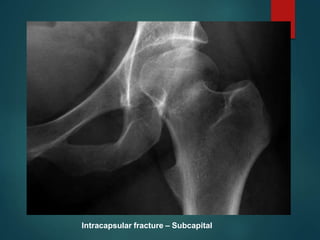

Intracapsular fracture – Subcapital

Femoral Neck Fractures

 Garden Classification

 I Valgus impacted

 II Non-displaced

 III Complete: Partially

Displaced

 IV Complete: Fully

 Functional

Classification

 Stable (I/II)

 Unstable (III/IV)